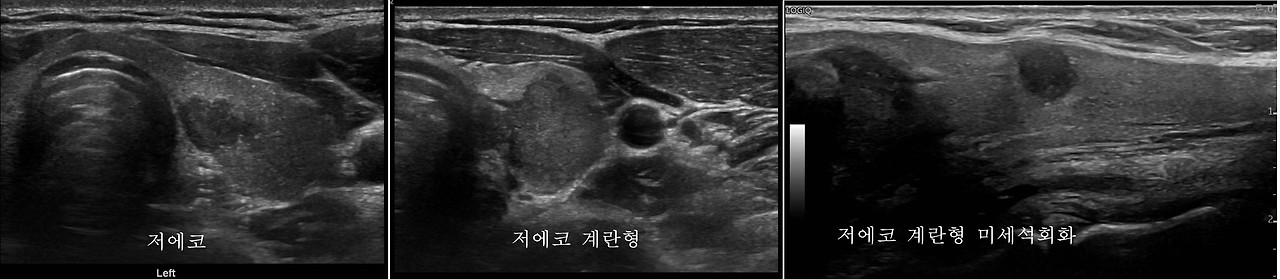

갑상선암의 진단은 다른 암에 비해서 진단이 어렵지 않습니다. 갑상선이 머리, 가슴처럼 뼈에 의해 보호되거나 복부 내 장기들처럼 깊게 있지 않기 때문입니다. 그래서 초음파로 쉽게 선별검사(screening)가 가능합니다. 초음파 후에는 필요에 따라 미세침 흡입 세포 검사를 시행하는데 침습적이긴 하지만, 이 또한 어렵지 않게 시행할 수 있습니다. 이후에는 경우에 따라 암유전자 검사, 중심부 생검 등을 시행하게 됩니다. 초음파에서 갑상선암의 특징은 저 에코음영(까맣게), 계란형(taller than wide), 불분명한 경계, 미세석회화 등이 있습니다. 그러나 갑상선암 중에서 60%-94.9%를 차지하는 유두암에서는 위의 소견을 보이지만 여포암에서는 이러한 특징을 보이지 않을 수 있습니다. 여포암의 초음파 소견은 양성 선종과 구분이 되지 않으며, 고에코/동등에코/저 에코, 분명한 경계를 가지는 균질한 고형종괴로 보이기도 합니다. 그러므로 갑상선암을 위한 선별검사로 초음파가 유용하지만 갑상선 여포암을 진단하는 데는 한계가 있습니다.